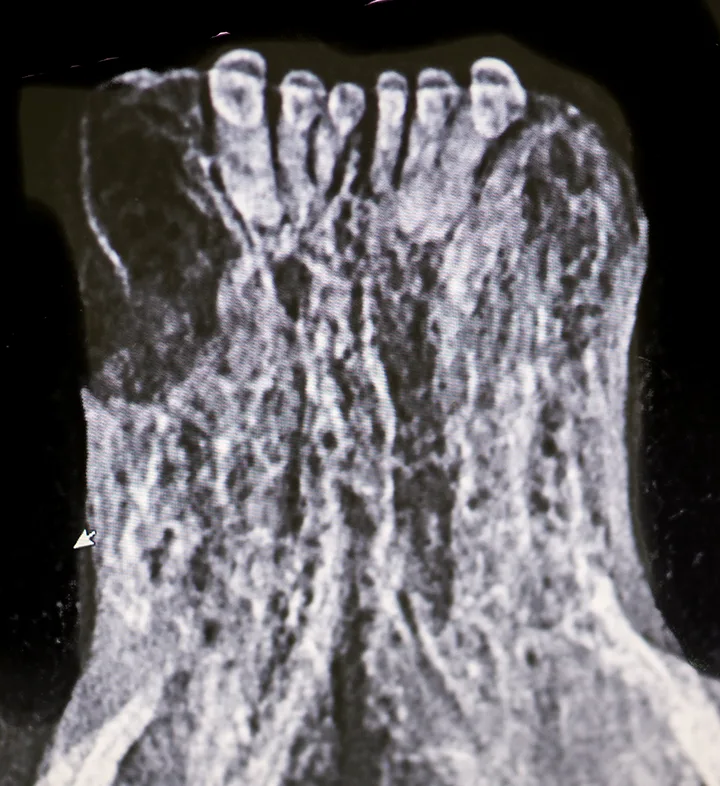

Tooth resorption type is determined via intraoral radiography based on root opacity and periodontal ligament space (see Types of Tooth Resorption Based on Radiographic Appearance and Figure 2).

Radiograph of a left mandibular molar tooth in a cat with Type 1 resorption (A) in which focal or multifocal radiolucency can be seen with otherwise normal radiopacity and normal periodontal ligament space. Radiograph of mandibular incisors and canine teeth in a cat with Type 2 resorption (B; white arrow) in which narrowing or disappearance of periodontal ligament space is present in at least some areas, and part of the tooth demonstrates decreased radiopacity. Radiograph of the right maxillary third and fourth premolars in a cat with Type 3 resorption (C); the third premolar features Type 1 resorption of the mesial root (arrowhead) and Type 2 resorption of the distal root (dashed arrow) with exposure to the oral cavity.